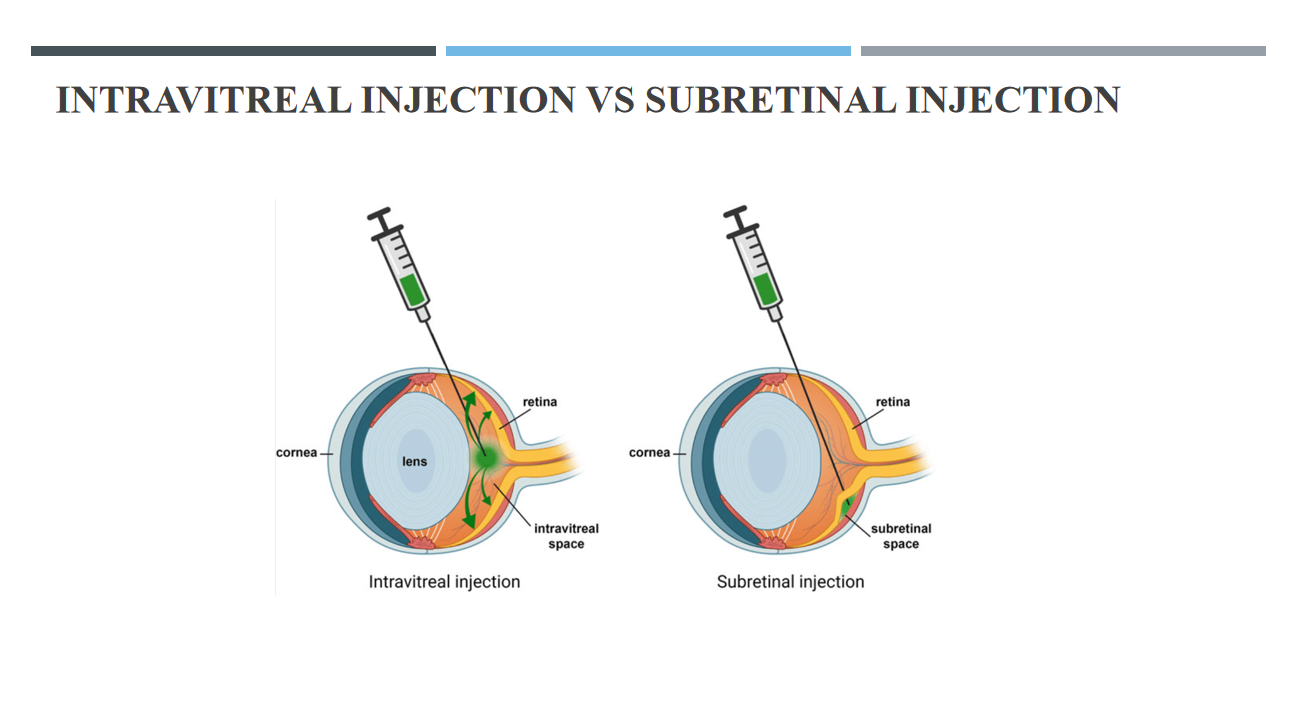

به گفته وی در این طرح که با هدایت سینا مظفری، عضو هیئت علمی دانشگاه علوم پزشکی مشهد و با همکاری مرکز تحقیقات چشم پزشکی دانشگاه علوم پزشکی شهید بهشتی اجرا شده، جهت افزایش انتقال ویروس در لایههای مختلف شبکیه در هنگام تزریق داخل زجاجیه که نوعی تزریق کمترتهاجمی است، جهشهایی در سطح پوشش ویروسی ایجاد شد. این جهشها به نفوذ بیشتر ویروس به تمام لایههای شبکیه کمک میکند. پس از تزریق ویروس تولید شده به درون چشم بیمار، ژن RPGR در گیرندههای نوری بیان میشود و از تخریب سلولهای شبکیه جلوگیری میکند.

به گفته این پژوهشگر در حال حاضر در دنیا ویروسهای AAV حامل ژن RPGR مورد استفاده در ژن درمانی بیماری رتینیت پیگمنتوزا وابسته به X بیشتر از نوع ۵ و ۸ است که برای تزریق از نوع زیرشبکیه مناسب است. در این اختراع برای اولین بار یک ویروس جدید AAV سروتیپ ۲ با نام AAV۲/۲.p (penta) YF/TV.GRK۱.coRPGRORF۱۵ ساخته شد که دارای جهشهای بیشتری در ژن کپسید است و این امر موجب افزایش پایداری و نفوذپذیری بالاتر ویروس میشود؛ بنابراین امکان تزریق مستقیم به درون زجاجیه چشم (به جای ناحیه زیرشبکیه) را به طور بسیار موثر و کارآمدی فراهم میکند و دیگر نیازی به تزریقهای بسیار تهاجمی زیرشبکیه که موجب التهاب شدید و همچنین جداشدگی شبکیه شده و در بیماران RP میتواند خطرناک باشد، نیست.

وی خاطرنشان کرد: ویروس تولید شده در این اختراع را میتوان با یک تزریق کمتر تهاجمی به درون زجاجیه تزریق کرد و این ویروس به دلیل نفوذپذیری بالا قادر به بیان ژن RPGR به صورت اختصاصی در گیرندههای نوری شبکیه – که در بیماران مبتلا به رتینیت پیگمنتوزا تخریب خواهد شد – میشود و بنابراین میتواند از آن جلوگیری نماید.